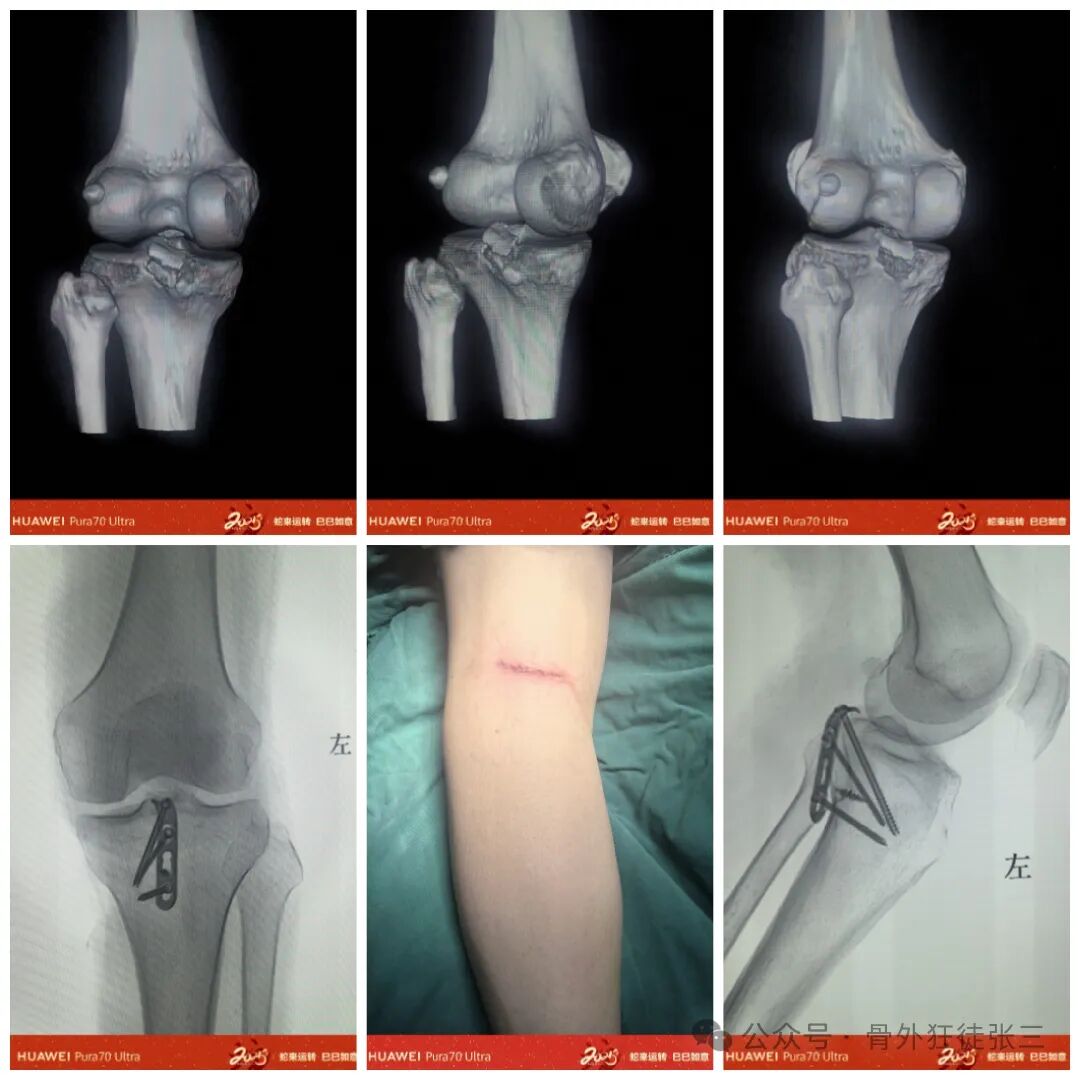

病例3

钩板+铆钉

手术切口

取膝关节后方平行腘窝横纹切口,可远端内侧延伸。

切开皮肤和皮下组织及筋膜,找到腓肠肌,沿腓肠肌内侧头中部的肌纤维将其部分切开;用拉钩将腓肠肌内侧头的内部和外部分开,显露后方关节囊并切开,显露撕脱骨折块即可。